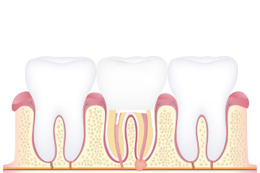

MTA 신경치료를 통해 신경을 보호합니다.

MTA 신경치료는 MTA(MINERAL TRIOXIDE AGGREGATE)라는 재료를 이용하여 흔히 치아신경이라 부르는 근관부위를 치료하는 술식입니다. MTA는 재료의 특성상 생체 조직의 적합성이 우수하고 밀폐성이 다른 기존 신경치료 재료에 비해 월등합니다.

MTA 신경치료 과정

01 구강검진

치아의 형태나 충치, 신경치료 계획 수립

02 충치·염증 제거

국소 마취 후 충치를 제거하고 뿌리 쪽 신경에 생긴 염증 제거

03 치아 조직 제거

신경관 소독 후 남아있는 치수 조직과 변성된 치아 조직 제거

04 채우기

치아 뿌리 내부를 MTA 충전재로 채우기

05 보철치료

치아 머리 부분을 보철로 수복